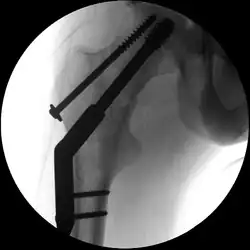

So genannte nichtdislozierte (also unverschobene) bzw. eingestauchte mediale Schenkelhalsfrakturen mit flachem Frakturneigungswinkel werden häufig mittels so genannter Zugschrauben behandelt (siehe Abbildung). Es handelt sich um hohle Schrauben, die über zuvor eingebrachte Führungsdrähte geschraubt werden (Lochschrauben). Bei jüngeren Patienten versucht man in der Regel, den Oberschenkelkopf zu erhalten. Auch hierzu werden Schrauben verwendet.[12]

- Zugschraubenosteosynthese bei einer medialen Fraktur. Behandlung einer nicht dislozierten medialen Schenkelhalsfraktur bei einer 92-jährigen Patientin.

Aufnahme vor der OP. a.p.-Aufnahme. Die Fraktur ist mit einem Pfeil markiert. -

Seitliche Aufnahme. Die Fraktur ist mit einem Pfeil markiert. -

Nach OP mit Zugschrauben, a.p.-Aufnahme. Man sieht die noch liegende Redondrainage. -

Seitliche Aufnahme.